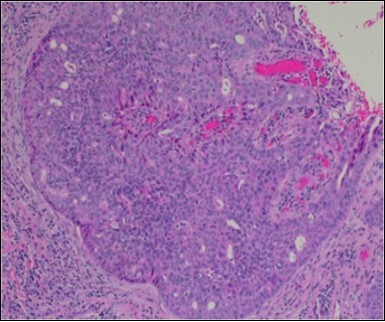

Granular arrangement of malignant cells and intercellular bridges are conspicuous with the demonstration of nuclear atypia, pleomorphism, prominent mitosis and tumour necrosis. A peripheral palisade is discernible within the cellular aggregates. Mitotic figures are common and can be quantified as up to 12 mitosis/ high power field. Tumour differentiation can prominently be of the ductal category with the demonstration of intra-cytoplasmic lumina. Comedo type tumour necrosis is evident along with foci of squamous differentiation The neoplasm is reactive to periodic acid Schiff ‘s (PAS) stain. (Figure 1, Figure 2, Figure 3, Figure 4, Figure 5, Figure 6, Figure 7, Figure 8, Figure 9, Figure 10, Figure 11, Figure 12, Figure 13.

Figure 4.Cellular atypia, mitosis and focal necrosis in eccrine porocarcinoma(16).

Classically, intra-epidermal and dermal nests of tumour cells exhibiting cellular atypia and enhanced mitotic activity are enunciated. Tumour aggregates articulate well demarcated, enlarged, atypical polygonal cells with indistinct cellular and nuclear outline, nuclear hyperchromasia , irregular nuclei, vesicular or prominent nucleoli and minimal eosinophilic cytoplasm. Polygonal tumour cells can depict central keratinisation 6, 7.

The neoplasm is composed of lobules of aberrant epithelial cells configured in cords with incrimination of the dermis and epidermis.. Malignant cells congregate within the epidermis or infiltrate the dermis, especially in the primary tumour. Tumour cells within tumour aggregates display a well demarcated cellular outline and appear distinct from encompassing squamous cells. Numerous tumour cell clusters demonstrate a cystic lumen. Prominent epidermal acanthosis is discerned on account of tumour cell proliferation 6, 7.